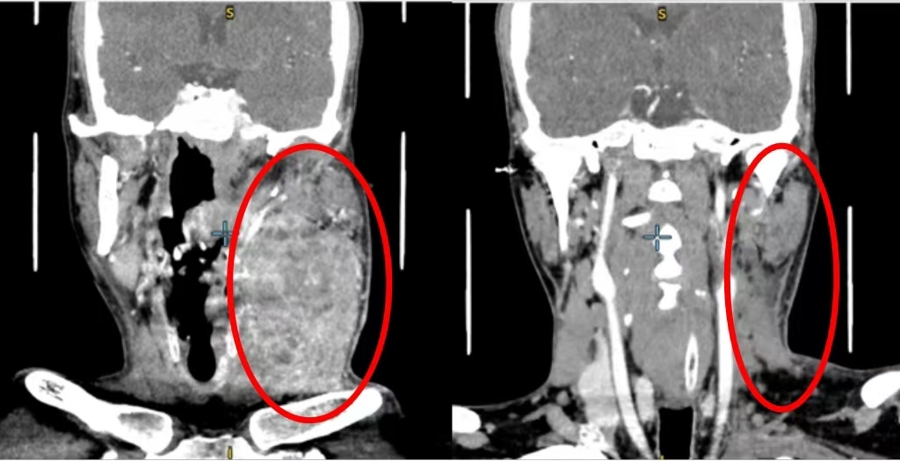

两个月前,患者许某发现左侧舌部出现溃疡,症状持续不见好转。经系统检查,他被确诊为左舌鳞状细胞癌(cT4aN3bM0)。此时,肿瘤已包绕左侧颈动脉,属于晚期高危病例,常规外科手术切除的难度与风险都极高。雪上加霜的是,患者首次就诊后,舌体肿瘤便发生破裂出血,被紧急送往上海第九人民医院急诊留观。

口腔颌面-头颈肿瘤科主任何悦教授接到首诊医生胡永杰主任医师的病情汇报后,第一时间发起首次多学科会诊,同时为患者开通诊疗绿色通道。放疗、肿瘤内科等亚专科专家共同研讨治疗方案。结合患者的病情、体质及经济状况,专家团队精准敲定“先行药物转化治疗,待肿瘤缩小后再行根治性手术”的个体化方案,采用靶向+免疫+化疗的联合治疗模式。经过规范治疗富盈网,患者肿瘤体积显著缩小,临床症状明显缓解,各项指标均达到外科手术指征,成功打破“不可手术”的僵局。